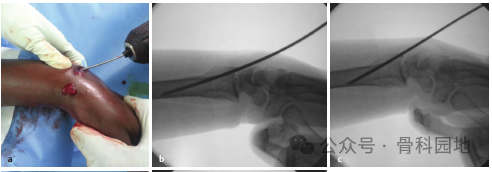

首先进行骨折闭合复位,牵引时须缓慢而持续,通过掌屈和尺偏来矫正背侧和桡侧移位。复位后,将手放在卷起的布单上,保持掌屈和尺偏(下图a,b),并用至少三根经皮克氏针固定。

第一枚克氏针在 Lister 结节进针,以 45°倾斜,瞄准桡骨长轴上近端骨块的掌侧皮层。如果进针点位于Lister结节的尺侧,可能会损伤拇伸肌腱。

第二枚克氏针自桡骨茎突远端 0.5 cm 处进针,克氏针与桡骨轴成 60°角,穿透骨折近端尺侧皮质。

第三枚克氏针在距腕关节线远端0.5 cm处,固定月骨窝骨块,位于第四和第五伸肌室之间。克氏针以 45 °角固定到桡骨的掌侧,如下图a、b 所示。